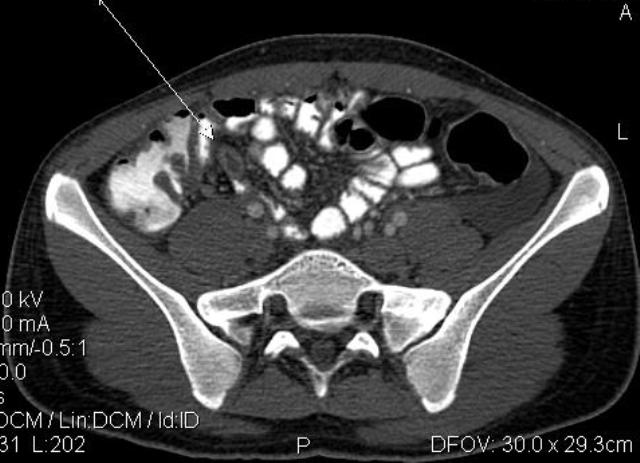

- Острый аппендицит, КТ MPR coronal

- AA Cor.jpg (18.44 КБ) 1330 просмотров